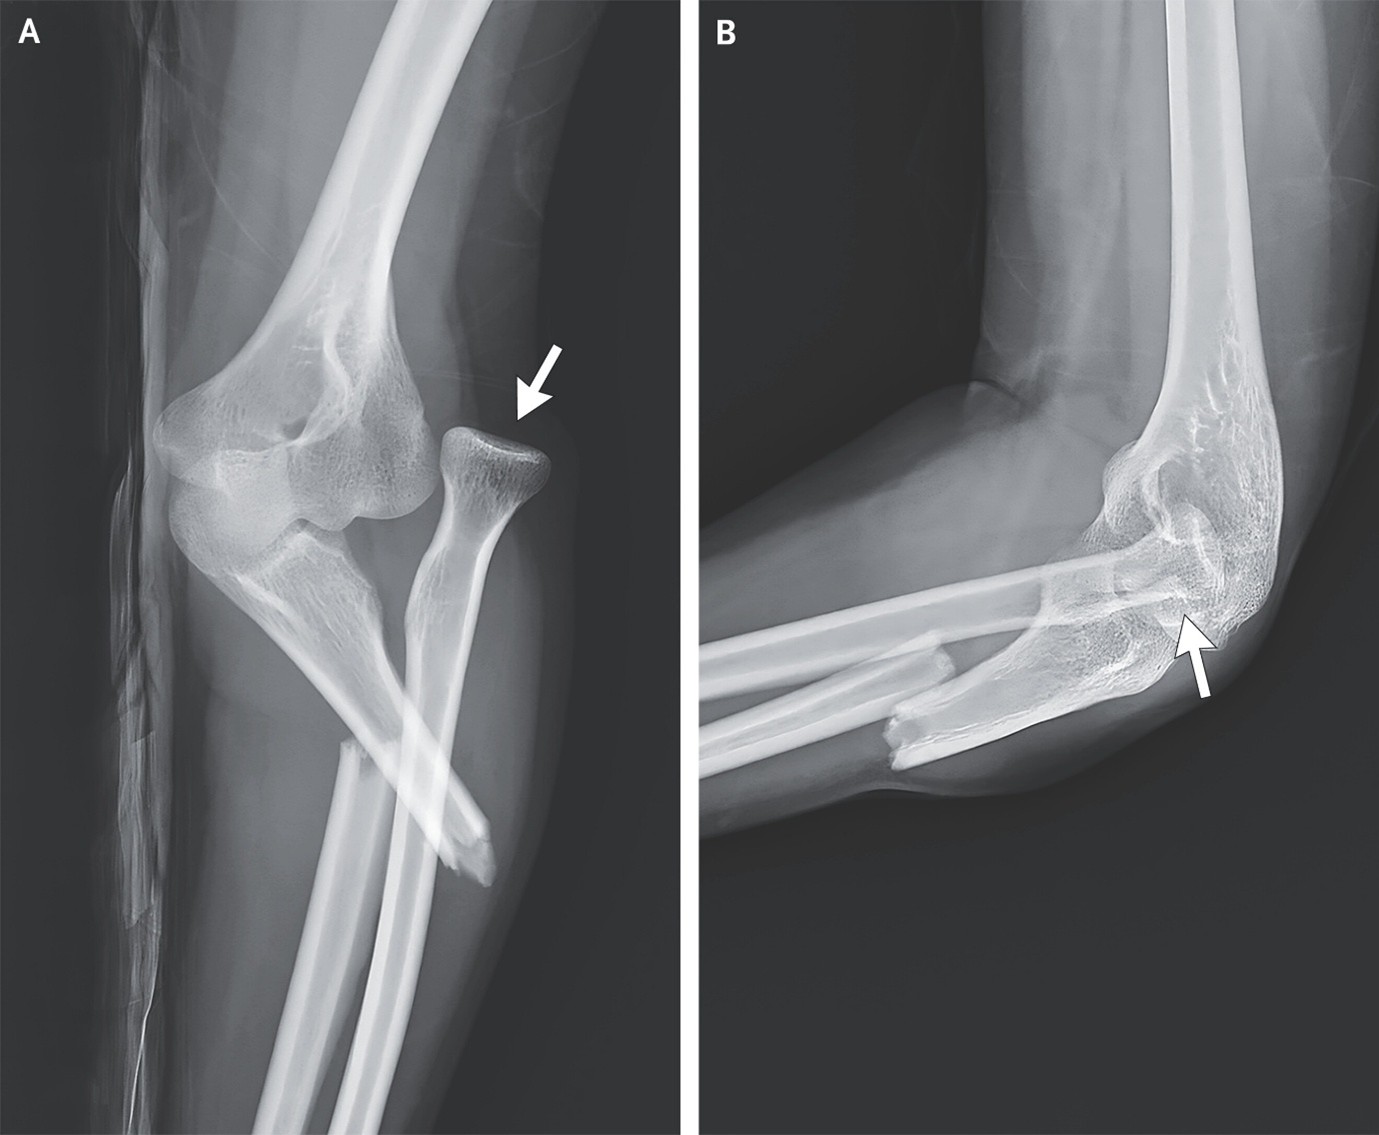

(10). Monteggia Fracture

Yen Cheng ChenPublished December 10, 2025, N Engl J Med 2025;393: e39, DOI: 10.1056/NEJMicm2510553, VOL. 393 NO. 23,

Abstract

A 26-year-old woman presented with left elbow pain after falling on an outstretched hand while ice-skating. Radiographs showed a fracture of the proximal third of the ulnar shaft and a posterior dislocation of the radial head.